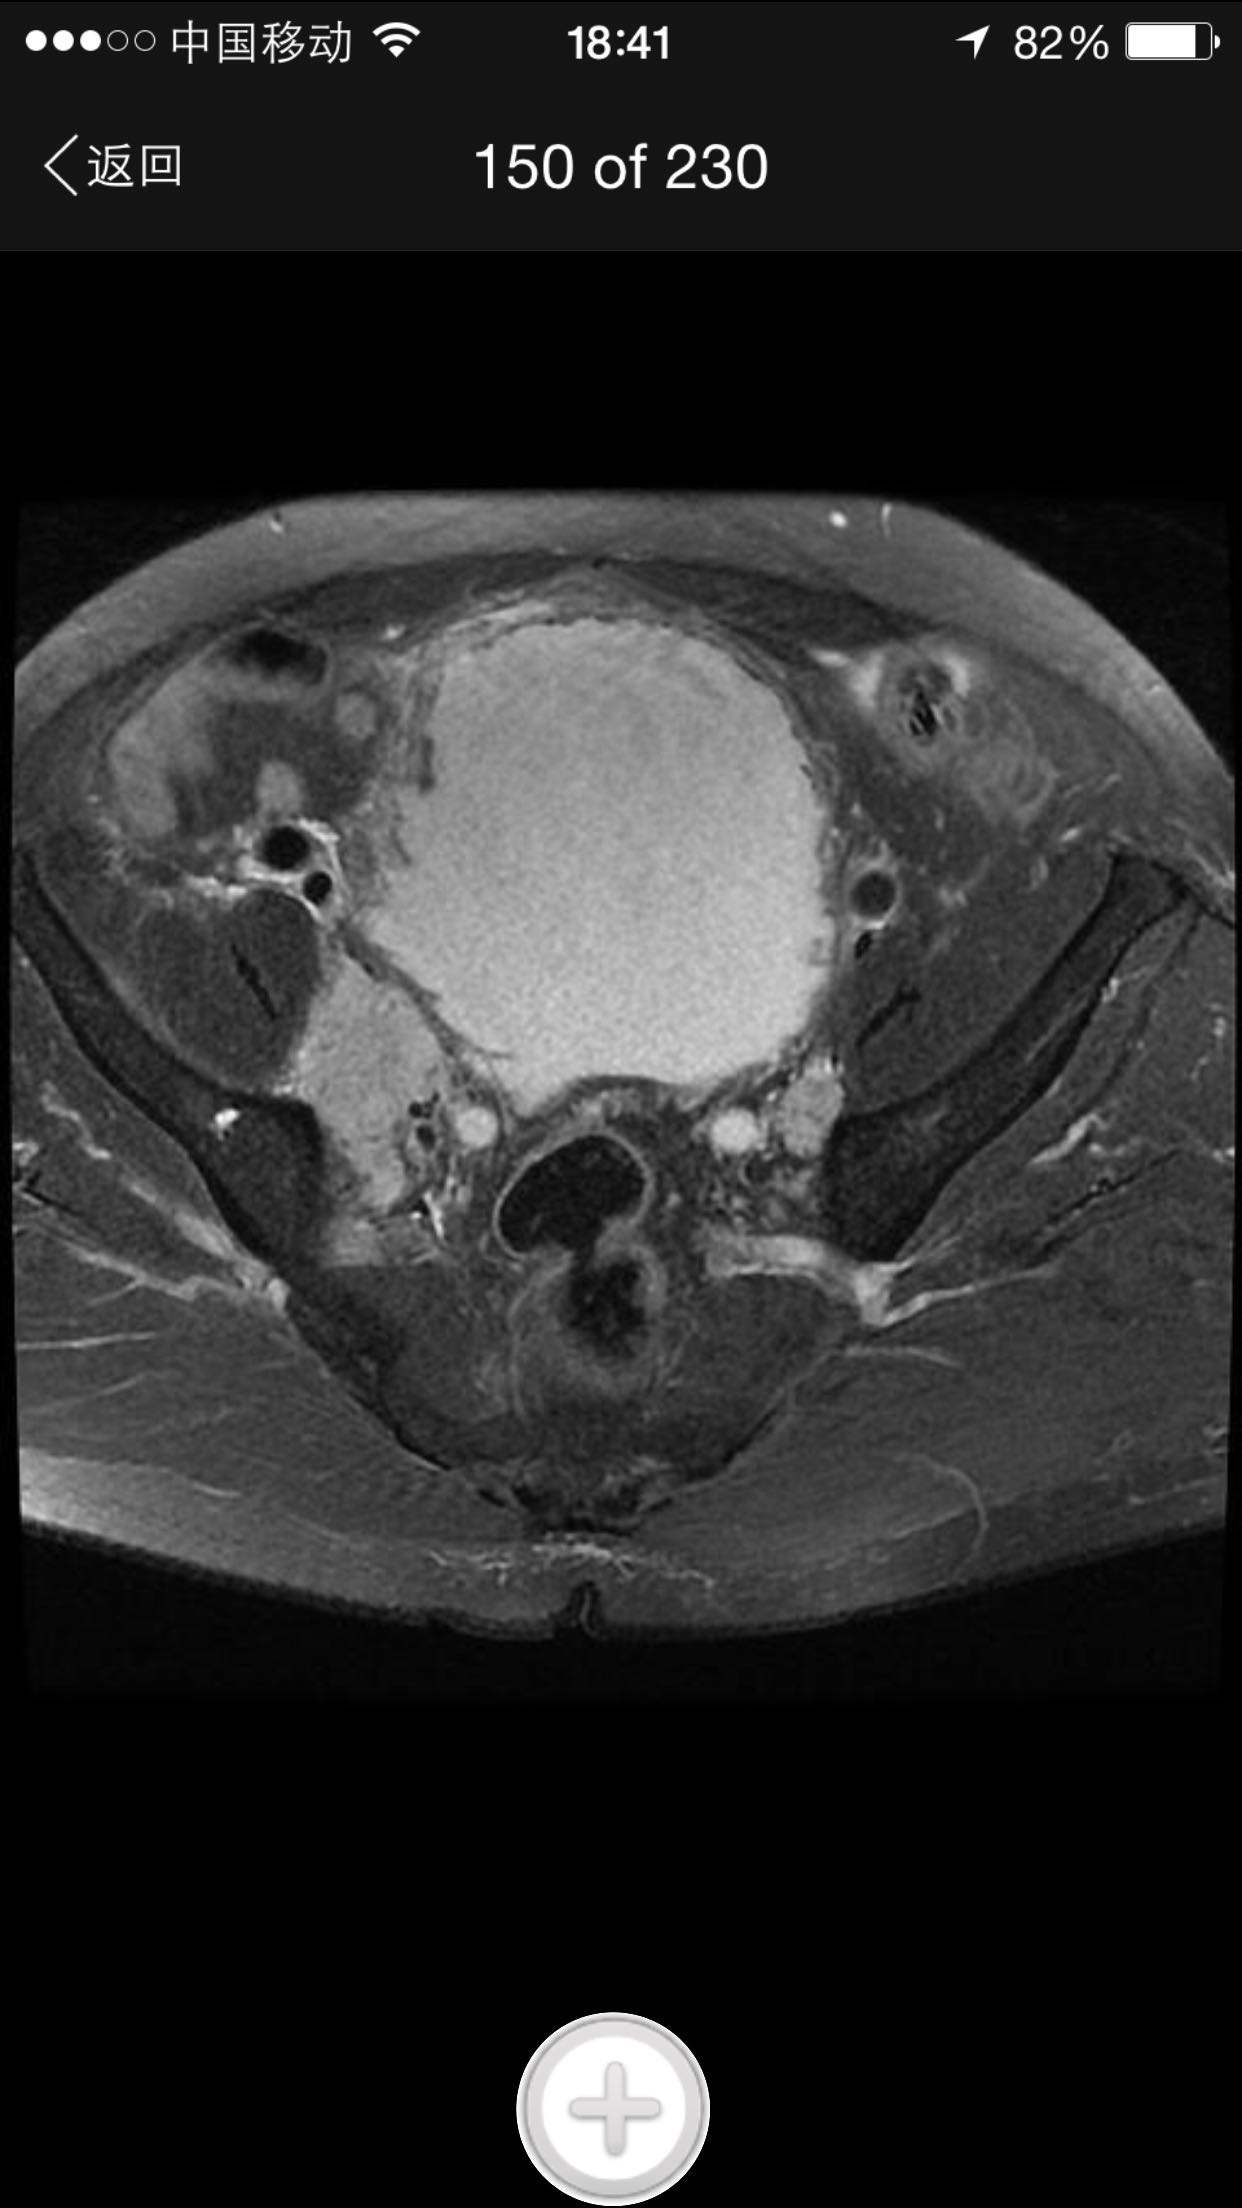

肛诊:前列腺增大,质硬,可扪及多个硬结。 PSA329ng/ml。

诊断:前列腺癌晚期 尿潴留 治疗:考虑患者临床分期较晚,T4期,且淋巴结转移,合并尿潴留,超声提示肾积水,决定行TURP,解决排尿困难。术中快速,如为前列腺癌,直接行手术去势。术中按上述方案处理。术后病理为前列腺中分化腺癌。